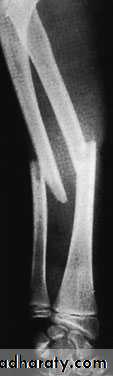

Fractures of the shafts of both forearm bones occur quite commonly. A twisting force (usually a fall on the hand) produces a spiral fracture with the bones broken at different levels. An angulating force causes a transverse fracture of both bones at the same level. A direct blow causes a transverse fracture of just one bone, usually the ulna.Bleeding and swelling of the muscle compartments of the forearm may cause circulatory impairment.

Both bones are broken, either transversely and at the same level or obliquely with the radial fracture usually at a higher level. In children, the fracture is often incomplete (greenstick) and only angulated.X-RAY